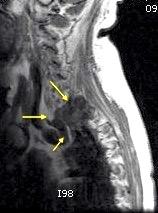

Empiema pleural izquierdo. Absceso del LID. Espondilodiscitis D11-D12.

Potsios C et al. Pyogenic Spondylodiscitis due to Streptococcus constellatus in an Immunocompromised Male Patient: A case Report and Review of the Literature. Case Reports in Infectious Diseases. 2019